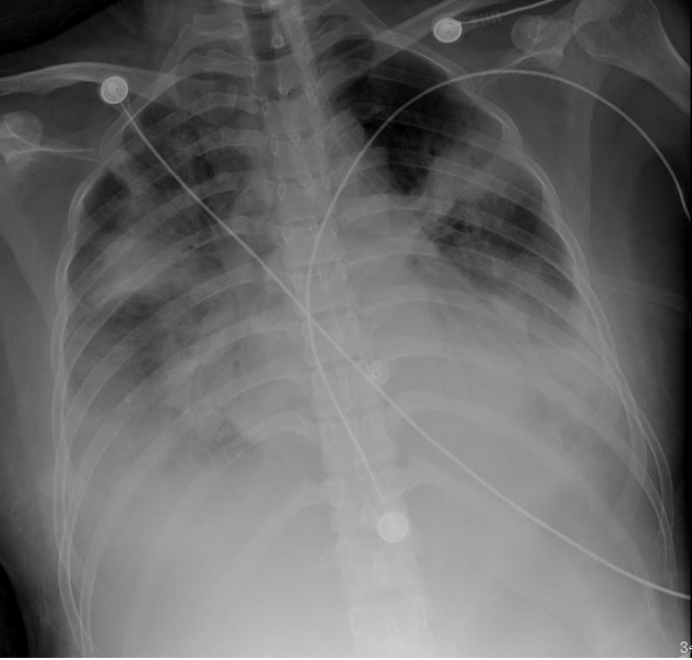

924下午开始进行俯卧位通气12 h。复查床旁胸片可见:9月24日(俯卧位前)右肺似乎略好,但左肺实变及下肺透亮度依然很差,没有完全膨胀。9月25日(俯卧位后第1天)双肺透亮度较前明显好转。9月27日(俯卧位后第3天)患者肺部病变持续好转(图9)。通过监测发现,俯卧位后,患者的静态肺顺应性明显好转(24→61 L/cmH2O)。

图片

9  俯卧位前后患者胸片变化情况